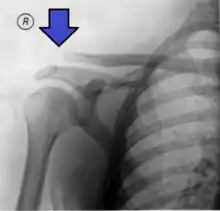

Acromion-clavicle disjunction (left shoulder) — note that the shoulder is lower and the "piano key"; the scar on the photograph and the screws on the radiography are ostheosynthesis material from a former trauma repair, without any connection with the present trauma.